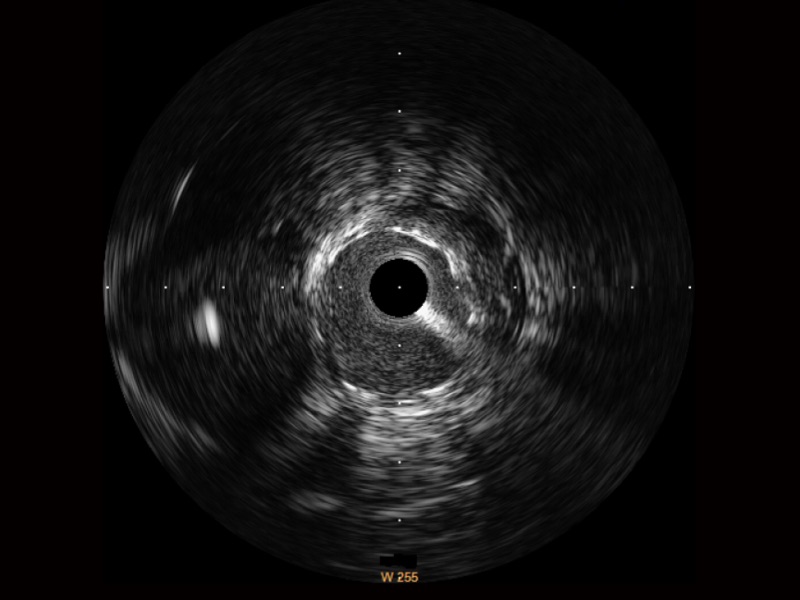

MILE米乐集团官网宽频IVUS图像

对比传统IVUS导管成像,MILE米乐集团官网宽频IVUS图像的近场支架梁显影更细腻,远场中膜外血管仍清晰可辨,兼顾远中近,兼顾分辨力与穿透深度